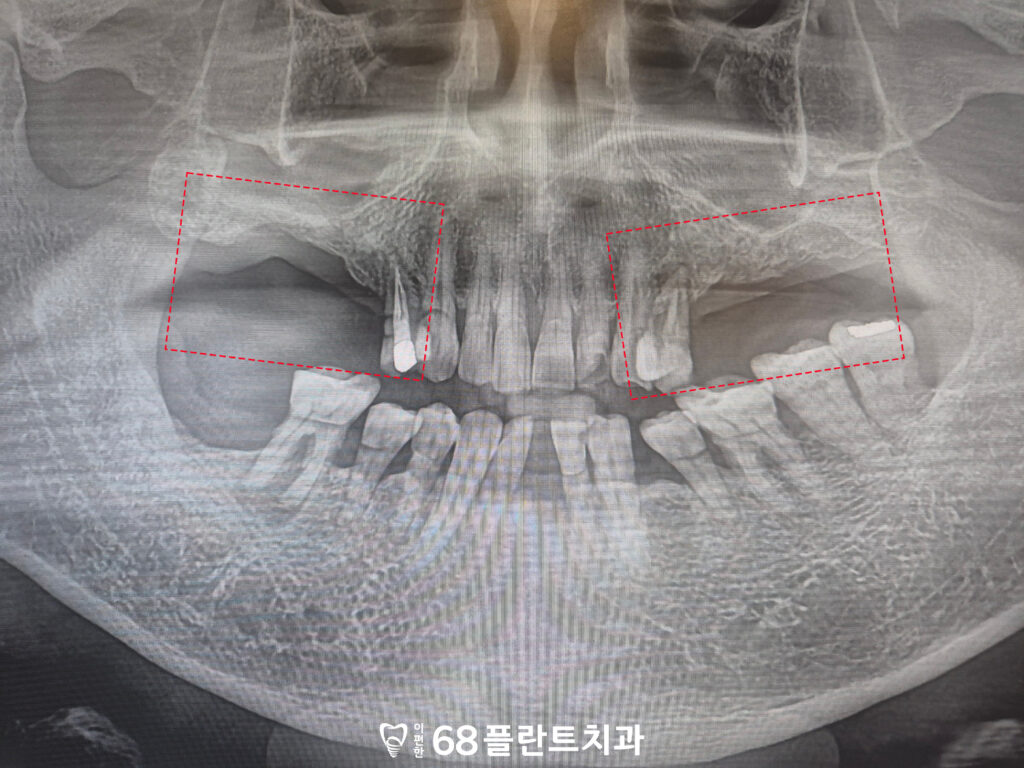

위 환자분께서는

양쪽 위 어금니가 소실된 이후

별도의 치료 없이 지내오시면서

식사 시 불편함을 느끼고,

씹을 수 있는 부위가 부족해져

내원해 주셨습니다.

확인해 보니

전체적으로 치주 상태와

치아 건강이 좋지 않았고,

양쪽 위 어금니가 상실된 상태로

오랜 시간이 경과하면서

해당 부위의 잇몸뼈 소실도

함께 진행된 상황이었습니다.

이러한 경우,

임플란트를 식립하여

치아의 기능을 회복하면 되지만

치아의 상실된 시기가 길었다보니

잇몸뼈가 많이 소실되어

식립할 공간이 부족했습니다.

특히 위쪽 어금니 부위에는

상악동이라 불리는 공기 공간이 위치해 있어,

잇몸뼈가 감소할 경우

임플란트를 바로 식립하기가

더욱 어려워질 수 있습니다.